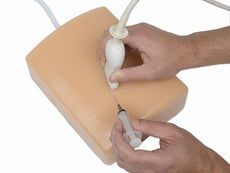

This CAE Blue Phantom foreign body single leg model is ideal for learning image acquisition and interpretation, and practicing the psychomotor skills necessary for ultrasound diagnosis, and ultrasound-guided procedures. Our patented Simulex tissue inserts allow learners to learn ultrasound system controls, positioning and moving the transducer and recognizing anatomy.

- Dimension: 32” long x 8” wide x 8” high (81 cm x 20 cm x 20 cm)

- Weight: 25 lbs. (11.5 kg)